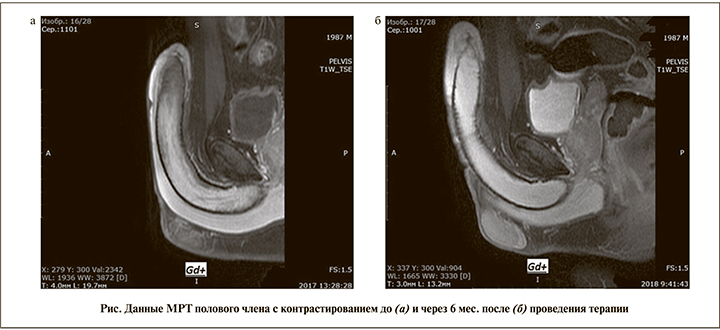

Магнитно-резонансная томография полового члена показала (см. рисунок, а) наличие локального низкого сигнала на Т2-взвешенных изображениях в дистальной части левого кавернозного тела в виде утолщения внутренней части белочной оболочки толщиной до 0,4 см, длиной до 2 см, с гетерогенным сигналом от обоих кавернозных тел в дистальной половине. После внутривенного введения МР-контрастного препарата (Gadolinium) отмечено отсутствие контрастирования участка в дистальном отделе левого кавернозного тела, что указывает на дистальный тромбоз слева, при этом проксимальные отделы кавернозных тел контрастировались полностью.

Поскольку данное обследование было выполнено через 5 дней после первичного обращения пациента, ему была скорректирована терапия. Ввиду исключения диагноза кавернита, а также отсутствия явной положительной динамики от терапии препараты первой линии были отменены и рекомендован длительный прием аспирина в дозе 160 мг в сутки. Через 1 мес. после начала лечения ацетилсалициловой кислотой пациент отметил стихание боли и через 3 мес. предъявлял жалобы только на наличие образования в области головки полового члена. Повторное УЗДГ полового члена через 3 мес. также выявило положительную динамику. По прошествии 6 мес. от начала терапии пациент отметил полное исчезновение симптомов, что было подтверждено данными контрольной МРТ полового члена с контрастированием (см. рисунок, б).